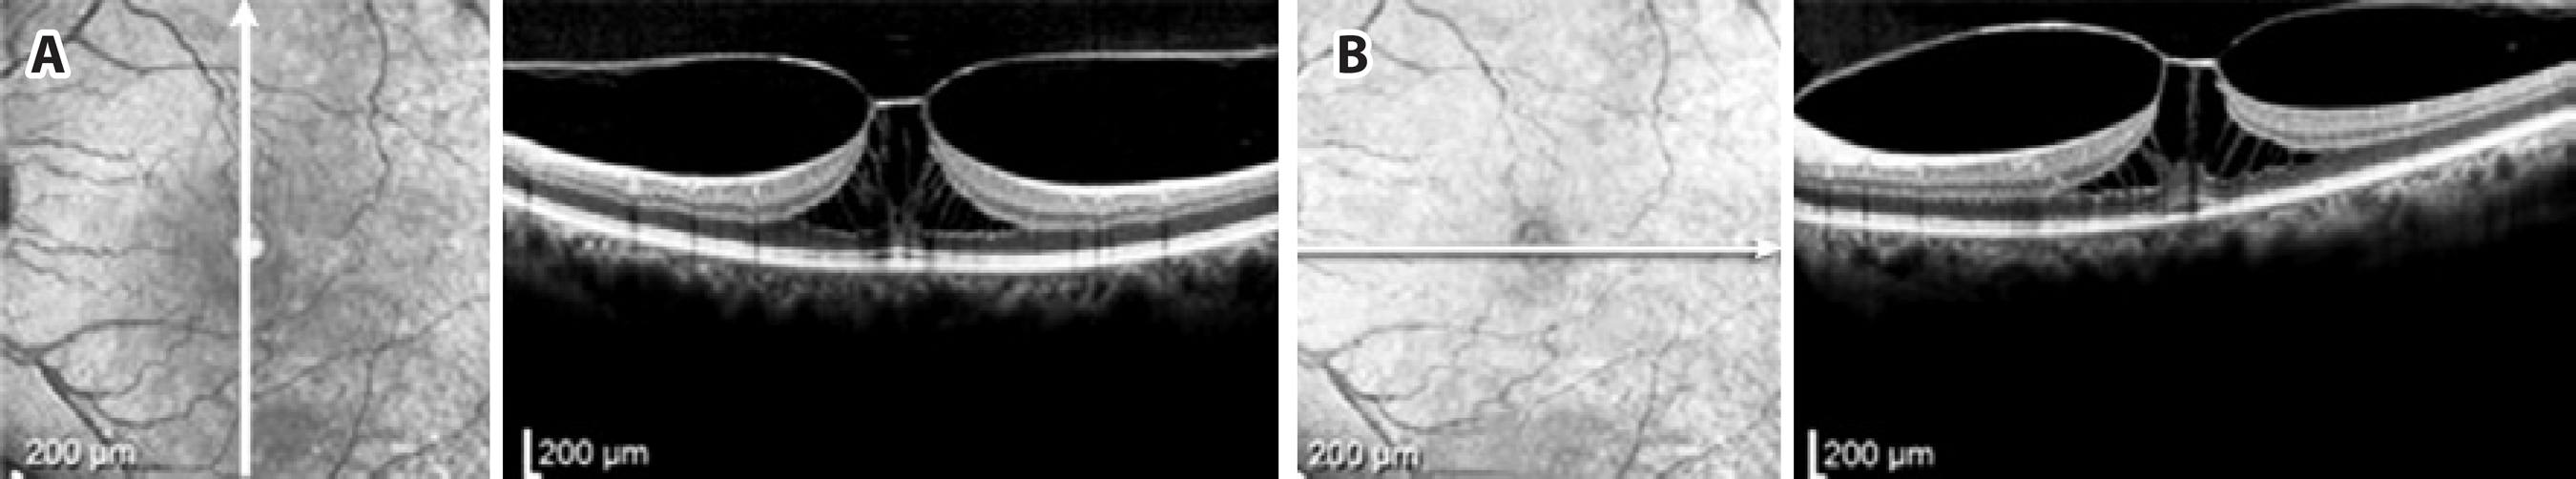

Figure 1 Initial Spectral Domain Optical Coherence Tomography (SD-OCT) of a 49-year-old phakic patient showing focal vitreo-macular traction (VMT) (A), with complete separation of the posterior hyaloid 4 days after ocriplasmin injection, accompanied by re-establishment of macular contours (B).